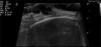

A 61-year-old woman, whose only relevant condition in her medical history was an operation for breast fibroadenoma, attended the clinic for a mildly painful, rapidly growing lesion in the right frontoparietal region, next to the hairline. The lesion had appeared 1 month earlier, a few days after trauma to the region. Physical exploration showed an exophytic lesion measuring 15mm across. This lesion was well defined and soft to the touch, of reddish and violaceous color with white-yellow patches (Figure 1). The dermatoscopic image showed a lesion with homogeneous red areas, irregular white-yellow structures, areas covered with a blue-white veil, irregular linear vessels, and some chrysalides (Figure 2). Skin ultrasound showed a hypoechoic, lobulated lesion in the superficial dermis, with discrete posterior reinforcement and increased perilesional vascularization (Figure 3). The lesion was completely excised under local anesthetic and sent for histopathological analysis, which confirmed the suspected diagnosis of anetodermic pilomatrixoma (Figure 4).

The ultrasound image of conventional pilomatrixoma shows a lesion with a hypoechoic halo and a central hyperechoic region (corresponding to calcification) that generates the posterior shadow.5 In 1999, Hughes et al.6 published a retrospective preoperative ultrasound study of 28 suspected conventional pilomatrixomas. In 20 of these, the ultrasound findings supported the suspected clinical diagnosis and in 16 of these 20 lesions, histological study confirmed diagnosis of pilomatrixoma. In the literature that we reviewed, we could not find a description of skin ultrasound of anetodermic pilomatrixoma.

Differential diagnosis should include basal cell carcinoma (BCC) and melanoma,4 and in both cases, the dermatoscopic and ultrasound studies can help in the preoperative diagnosis. From the ultrasound point of view, BCC and melanoma are also considered hypoechoic lesions. The characteristics that can help differentiate these lesions from pilomatroxima are the presence of small hyperechoic nodules in the lesion characteristic of BCC and an irregular border with abundant vascularization within the tumor in characteristic melanoma lesions.7,8